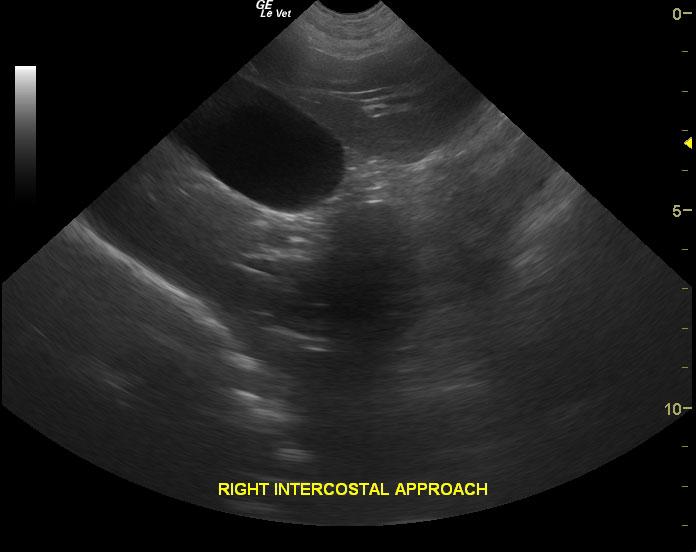

An 8-year-old FS Great Dane dog with a history of urinary tract infection and VPCs was presented for evaluation of lethargy and weakness in the hind limbs. Elevated ALP activity and BUN was present on serum biochemistry.

An 8-year-old FS Great Dane dog with a history of urinary tract infection and VPCs was presented for evaluation of lethargy and weakness in the hind limbs. Elevated ALP activity and BUN was present on serum biochemistry.